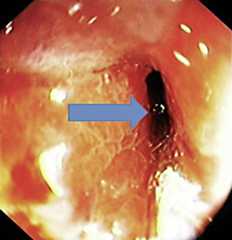

Fig. 2.

A deflated 17 mm guidewire-bearing dilating balloon, 5.5 cm long (Rigiflex, Boston Scientific, Nattick, Mass., USA) was passed through the endoscope and advanced through the stricture over the guidewire under direct endoscopic guidance (yellow arrow). The balloon was inflated to maximum pressure according to the manufacturer's instructions (red arrow).